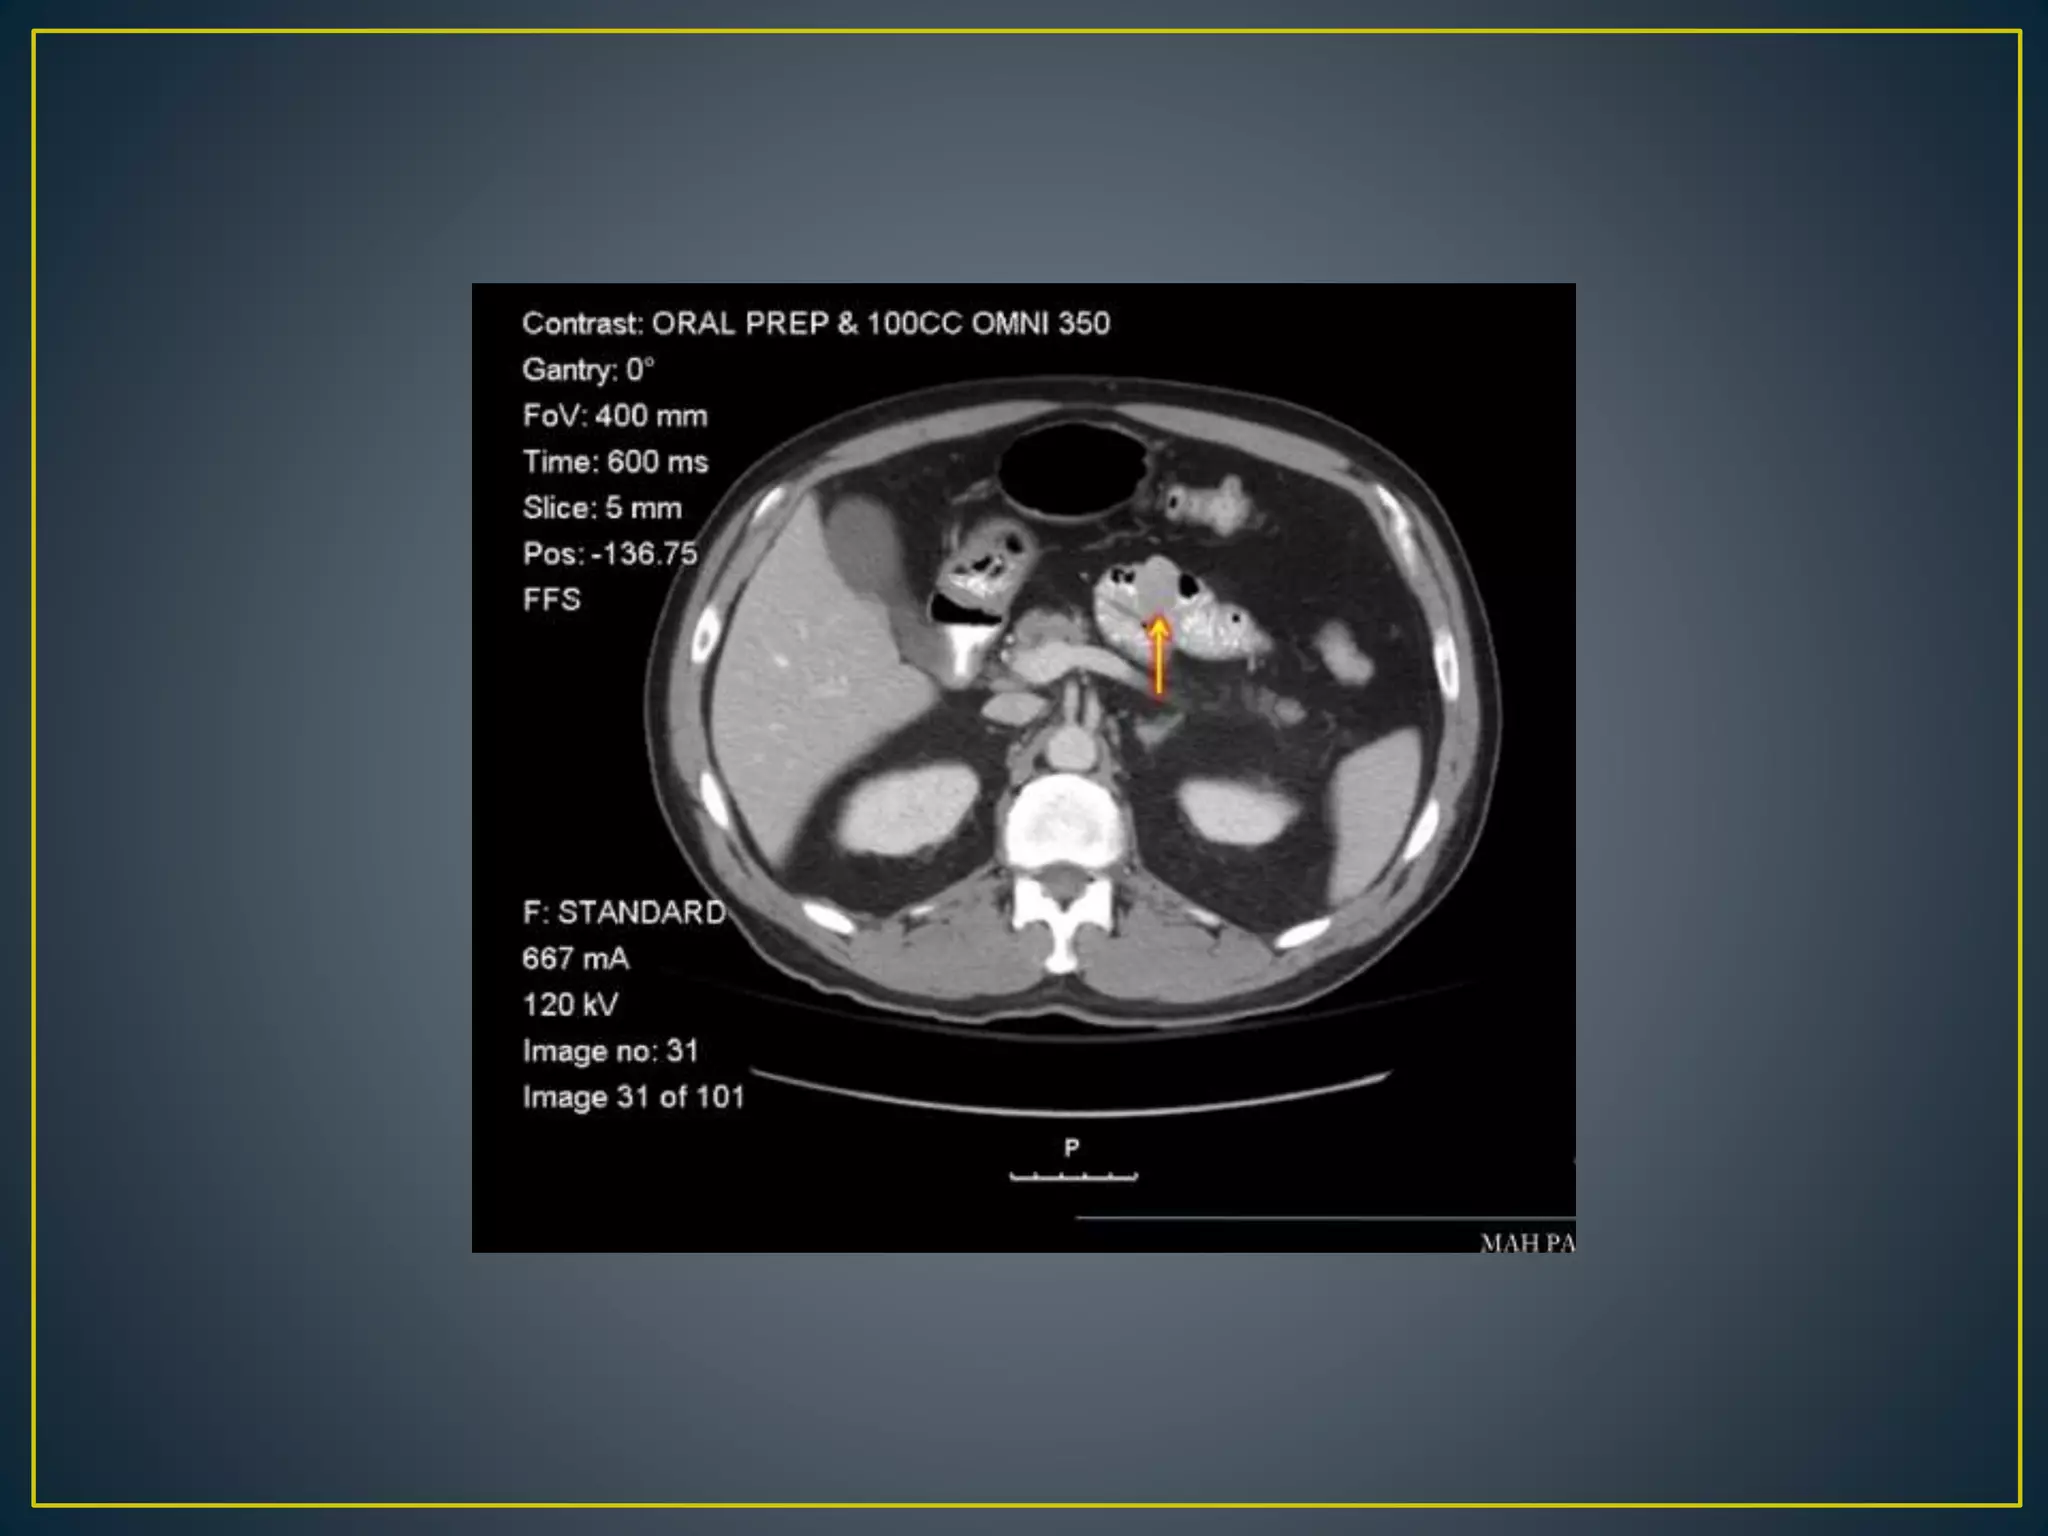

• Recent advancesin CT technology allowing thinner collimation, faster scanning times, greater anatomic coverage, and better multi-planar reformatted (MPR) images have greatly expanded the diagnostic role of CT angiography for GI BLEEDING • The CT angiographic diagnosis of active gastrointestinal bleeding is made when hyper attenuating extravasated contrast material is seen within the bowel lumen . The extravasated contrast material may demonstrate linear, jet like, swirled, ellipsoid, or pooled configurations or may fill the entire bowel lumen, resulting in a hyper- attenuating loop

• 31.

• 32.